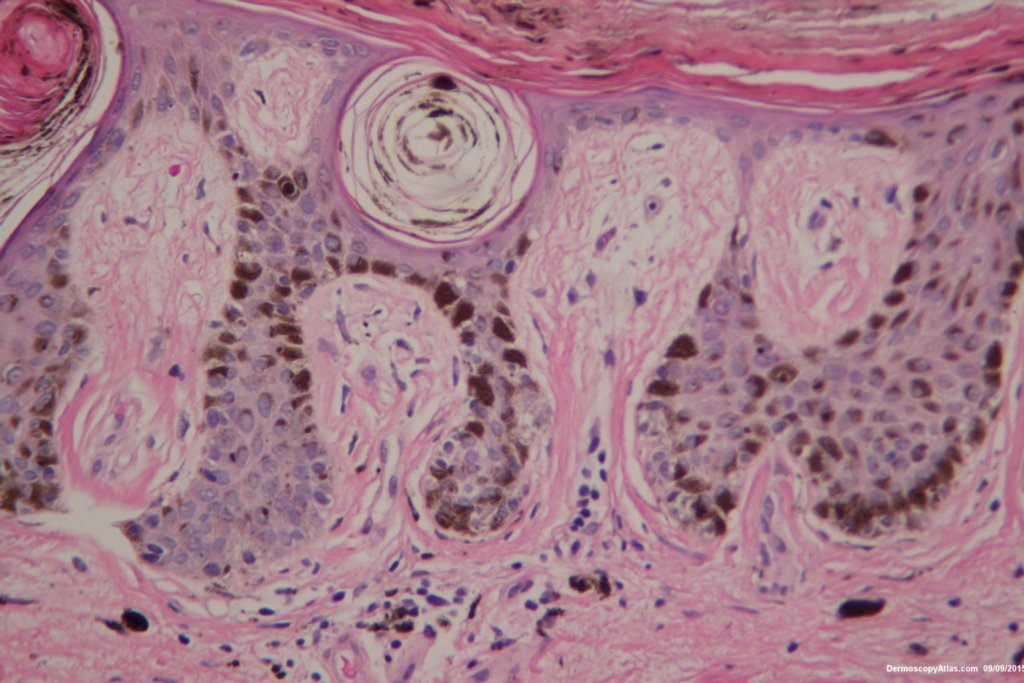

Image Number #3386 (Nevus junctional dysplastic lentiginous)

Diagnosis: Nevus junctional dysplastic lentiginous

Patient aged 92 noted to have this new lesion on the lower back. Note the extruded melanin on the stratum corneum and the lentiginous spread of melanocytes at the dermo epidermal junction. The dermatoscopy is symmetrical with multiple central clods presumably from the pigment in the stratum corneum. Tape stripping would have helped here.

Reported as a benign dysplastic junctional nevus. Special stains failed to show any upward spread of the melanocytes.